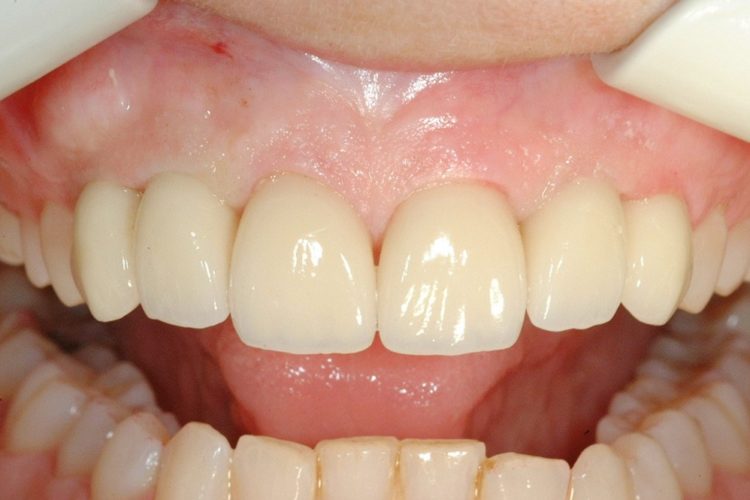

Caso Clínico: Paciente com Agnéisia Dentária Grave Descrição: Paciente com 37 anos com mobilidade nos 4 dentes de leite (laterais e caninos superiores), com aparência estética anterior desfavorável que pretende uma melhoria do sorriso. A solução passou pela extração dos dentes decíduos, pela colocação de 4 implantes NobelBiocare ®, 4 pilares em Zircónio, pela preparação